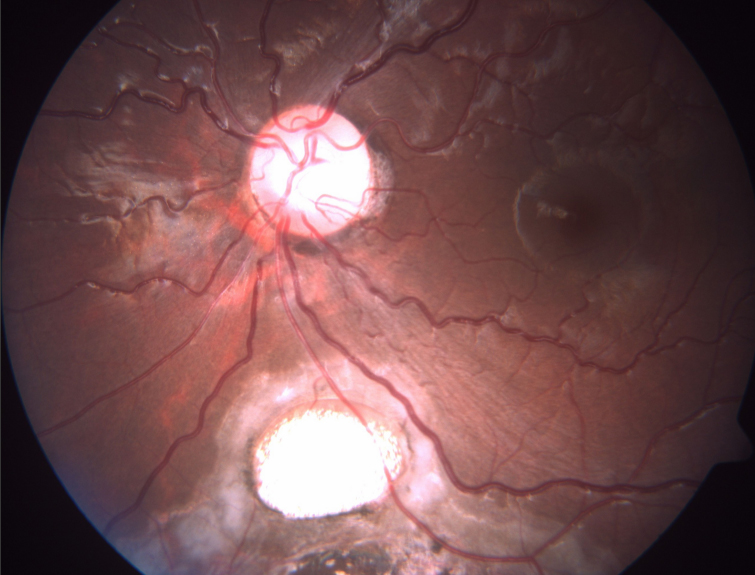

Figure 3 of Kumar, Mol Vis 2011; 17:1414-1419.

Figure 3. Fundus photograph in type V coloboma.